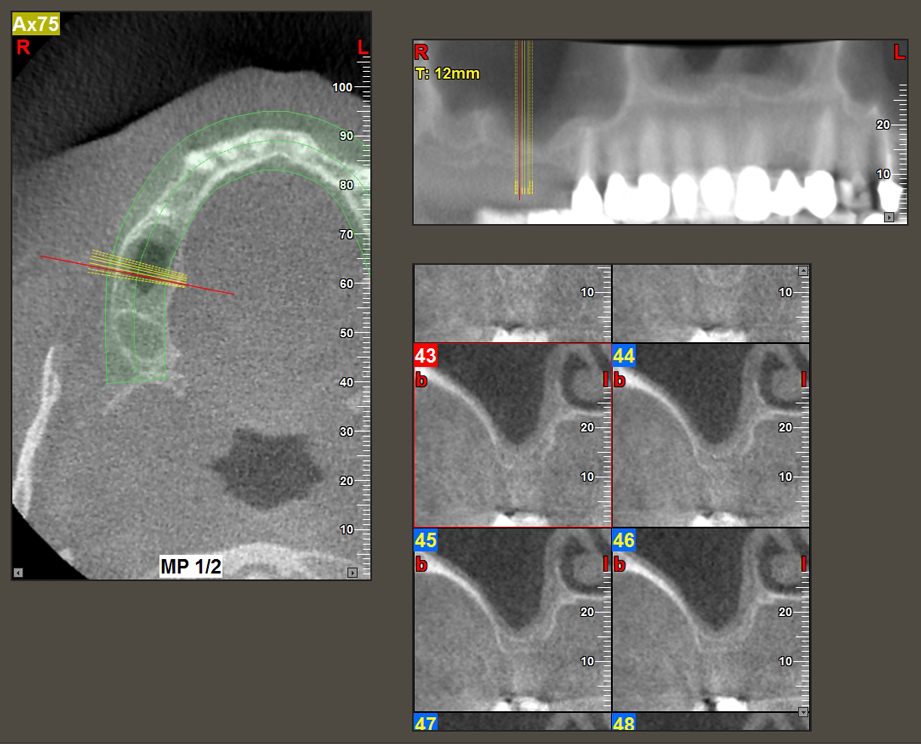

Una paziente di 49 anni, non fumatrice e con un'anamnesi priva di elementi rilevanti, è stata indirizzata al nostro studio di chirurgia orale per l'estrazione chirurgica del dente 16 ed il successivo impianto. Dopo l'estrazione, la paziente ha accusato dei lievi dolori causati dalla sinusite, motivo per cui abbiamo inizialmente aspettato sei mesi prima di procedere con l'intervento. L'altezza ossea residua in corrispondenza della posizione dell'impianto misurava 3-4 mm (Fig. 1 e 2).